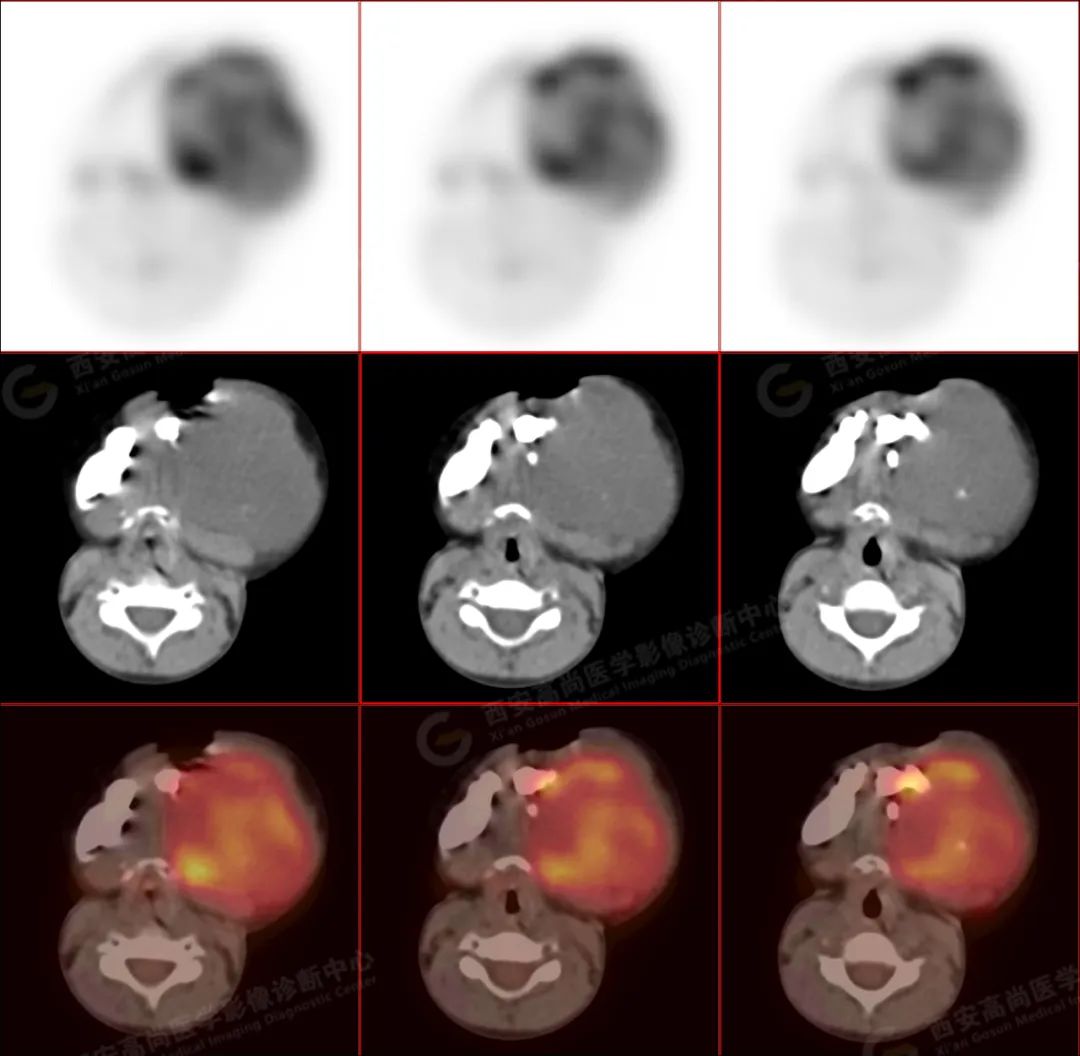

左侧下颌区可见巨大团块状软组织肿块,大小约 6.6 cm×5.8 cm×6.1 cm,向上达左侧颞下窝上缘,向下达下颌前联合,相邻左侧咬肌、颊肌等肌肉组织分界不清楚,左侧口底、咽部、腮腺受压改变,肿瘤包绕及侵犯左侧上颌升支、蝶骨翼突外板,呈 FDG 代谢不均匀异常增高,考虑为恶性病变,横纹肌肉瘤可能性大。

3.PET/CT 能够提供肿瘤代谢信息,并且提供肿瘤分期。分化程度越差的病灶 FDG 代谢明显增高。